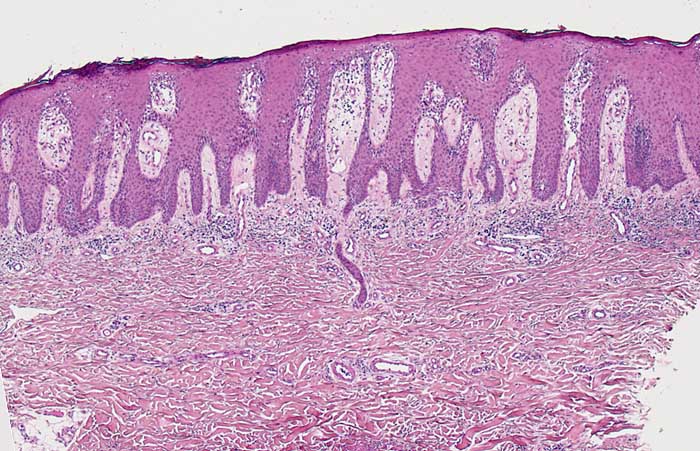

PathoPic – image database / PathoPic ID 6833 - Psoriasis vulgaris

Psoriasis vulgaris

Regelmässige Akanthose und stark elongierte gleichlange Reteleisten. Das Stratum granulosum fehlt weitgehend. Leichte Spongiose der unteren Epidermisabschnitte. Ödematöse Papillen mit gewundenen ektatischen Kapillarknäueln reichen bis nah an die Hautoberfläche heran. Oberflächliches perivsakuläres und interstitielles lymphozytäres Infiltrat. Das Stratum corneum ist hier nur sehr dünn.

Die Histomorphologie ist stadienabhängig. Das Bild zeigt eine vollentwickelte Läsion.